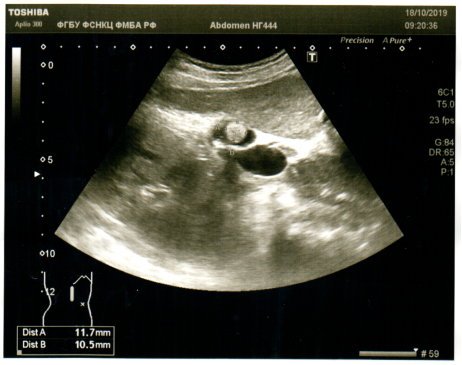

Конкремент в холедохе